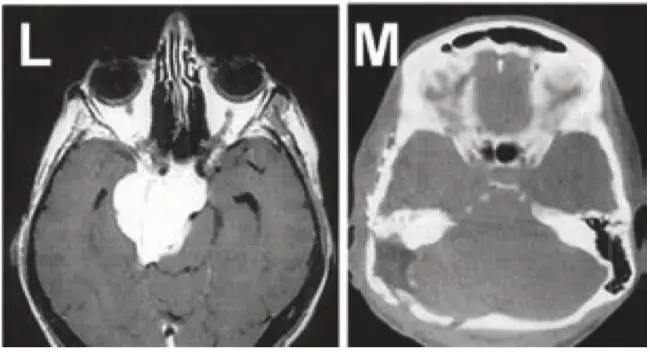

圖L+M

圖L+M:巖斜區(qū)腦膜瘤患者,術(shù)前術(shù)后的影像對(duì)比